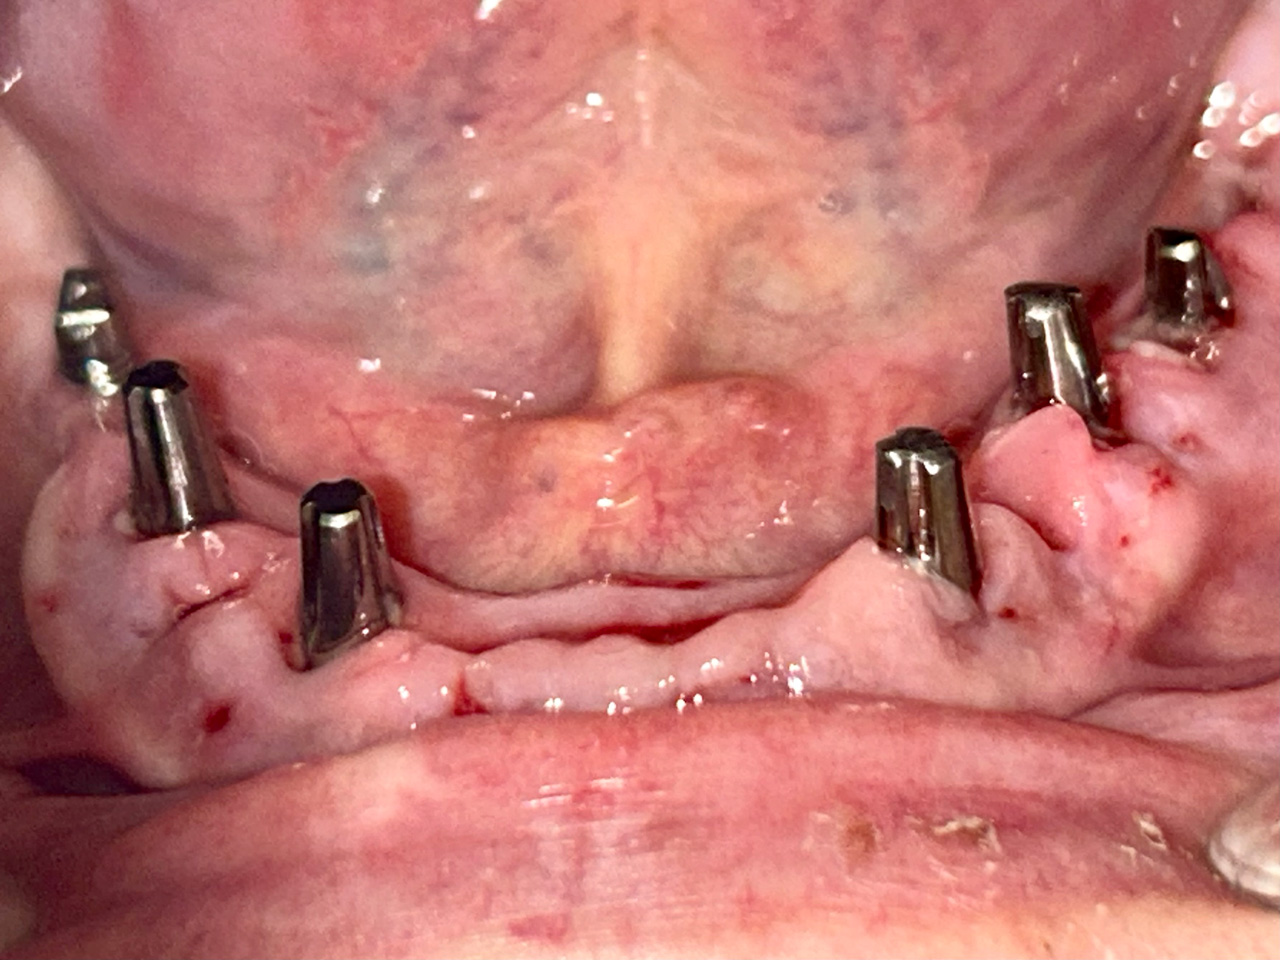

Alsó állcsont teljes rehabilitációja 72 óra alatt

Alsó állcsont teljes rehabilitációja 72 óra alatt, azonnal terhelhető implantátumokkal súlyos paradontitisben szenvedő dohányzó páciens esetében. Az alsó állcsont fogai mind mozogtak az előrehaladott fogágypusztulás miatt.

A fogakat eltávolítottuk, a gyulladt, fertőzött csontot kitakarítottuk, kifertőtlenítettük, majd azonnal implantáltunk.

Svájci, IHDE márkájú, azonnal terhelhető implantátumokat helyzetünk be, és ezekre harmadnapra rögzített, hosszútávú, fémvázas, esztétikus műanyaggal leplezett hidat ragasztottunk be.

Ezt az ideiglenes hidat a sebek gyógyulása miatt használjuk, de tartóssága miatt véglegesként is használható.

A legtöbb esetben, ahogy itt is, 6 hónap múlva porcelán hídra cseréljük, a teljes gyógyulás után.